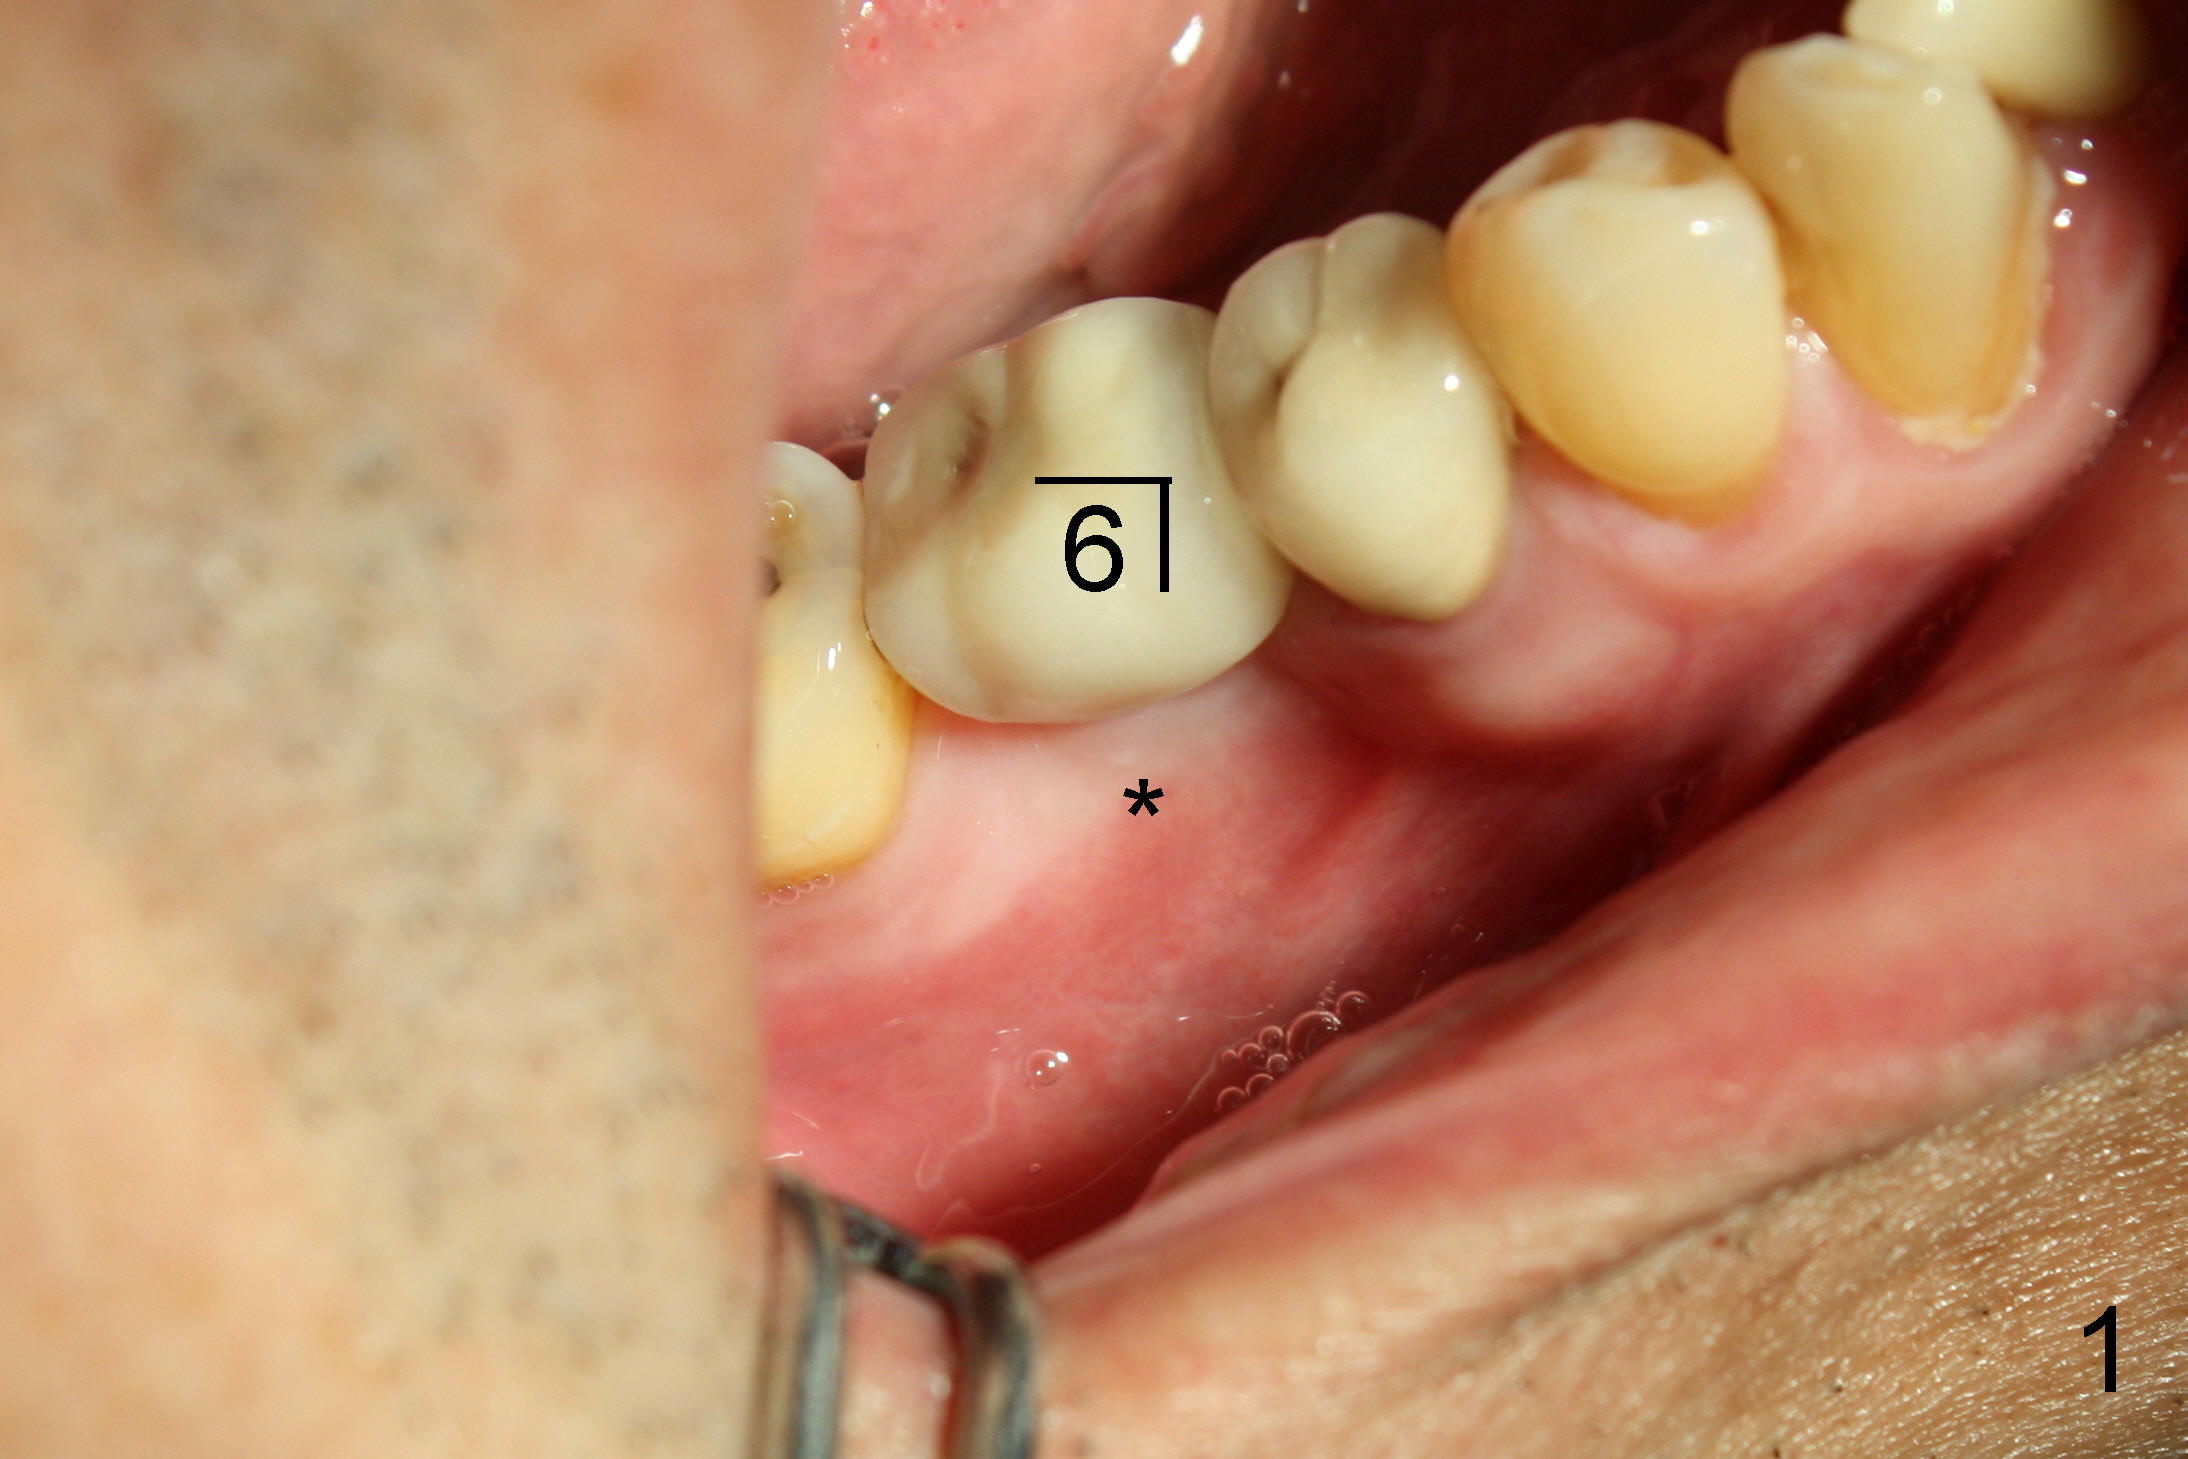

一两年前吴先生右下第一磨牙植牙偏舌侧(图一颊侧观,*:颊侧牙槽骨凹陷;图二镜影观,*:舌侧暴露植牙(光滑部分),但是他非常满意,他的论点是我们应该趁年轻,换所有该换的器官(包括牙齿)!

检查证实左下六颊侧骨板没有萎缩(图三,与图一对比),是立刻植牙适应症。不过根分叉牙龈没有红肿,探诊没有触痛,问病人疼痛性质,“刺痛”,再次仔细检查左下象限(图三),发现一个问题。那是什么呢?